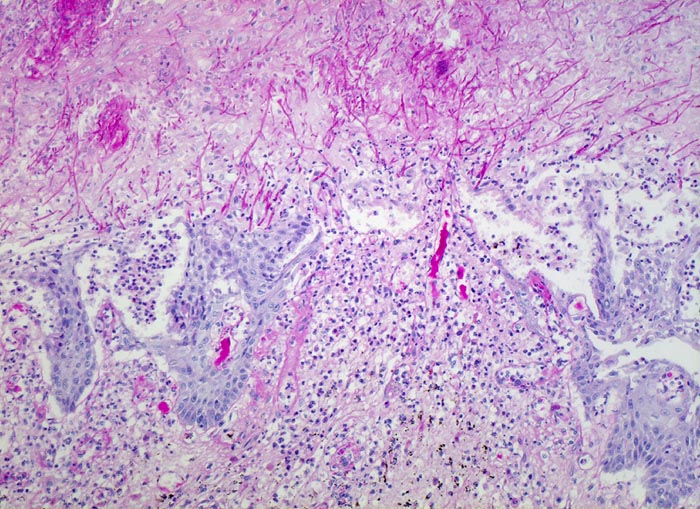

Das Plattenepithel ist teils ulzeriert, teils erodiert. Soorpseudohyphen infiltrieren das stehengebliebene Epithel. Dichte Infiltrate von neutrophilen Granulozyten im Epithel.

Mann, 75 Jahre, mit bekanntem multiplen Myelom. Autopisepräparat. Progrediente Dysphagie.